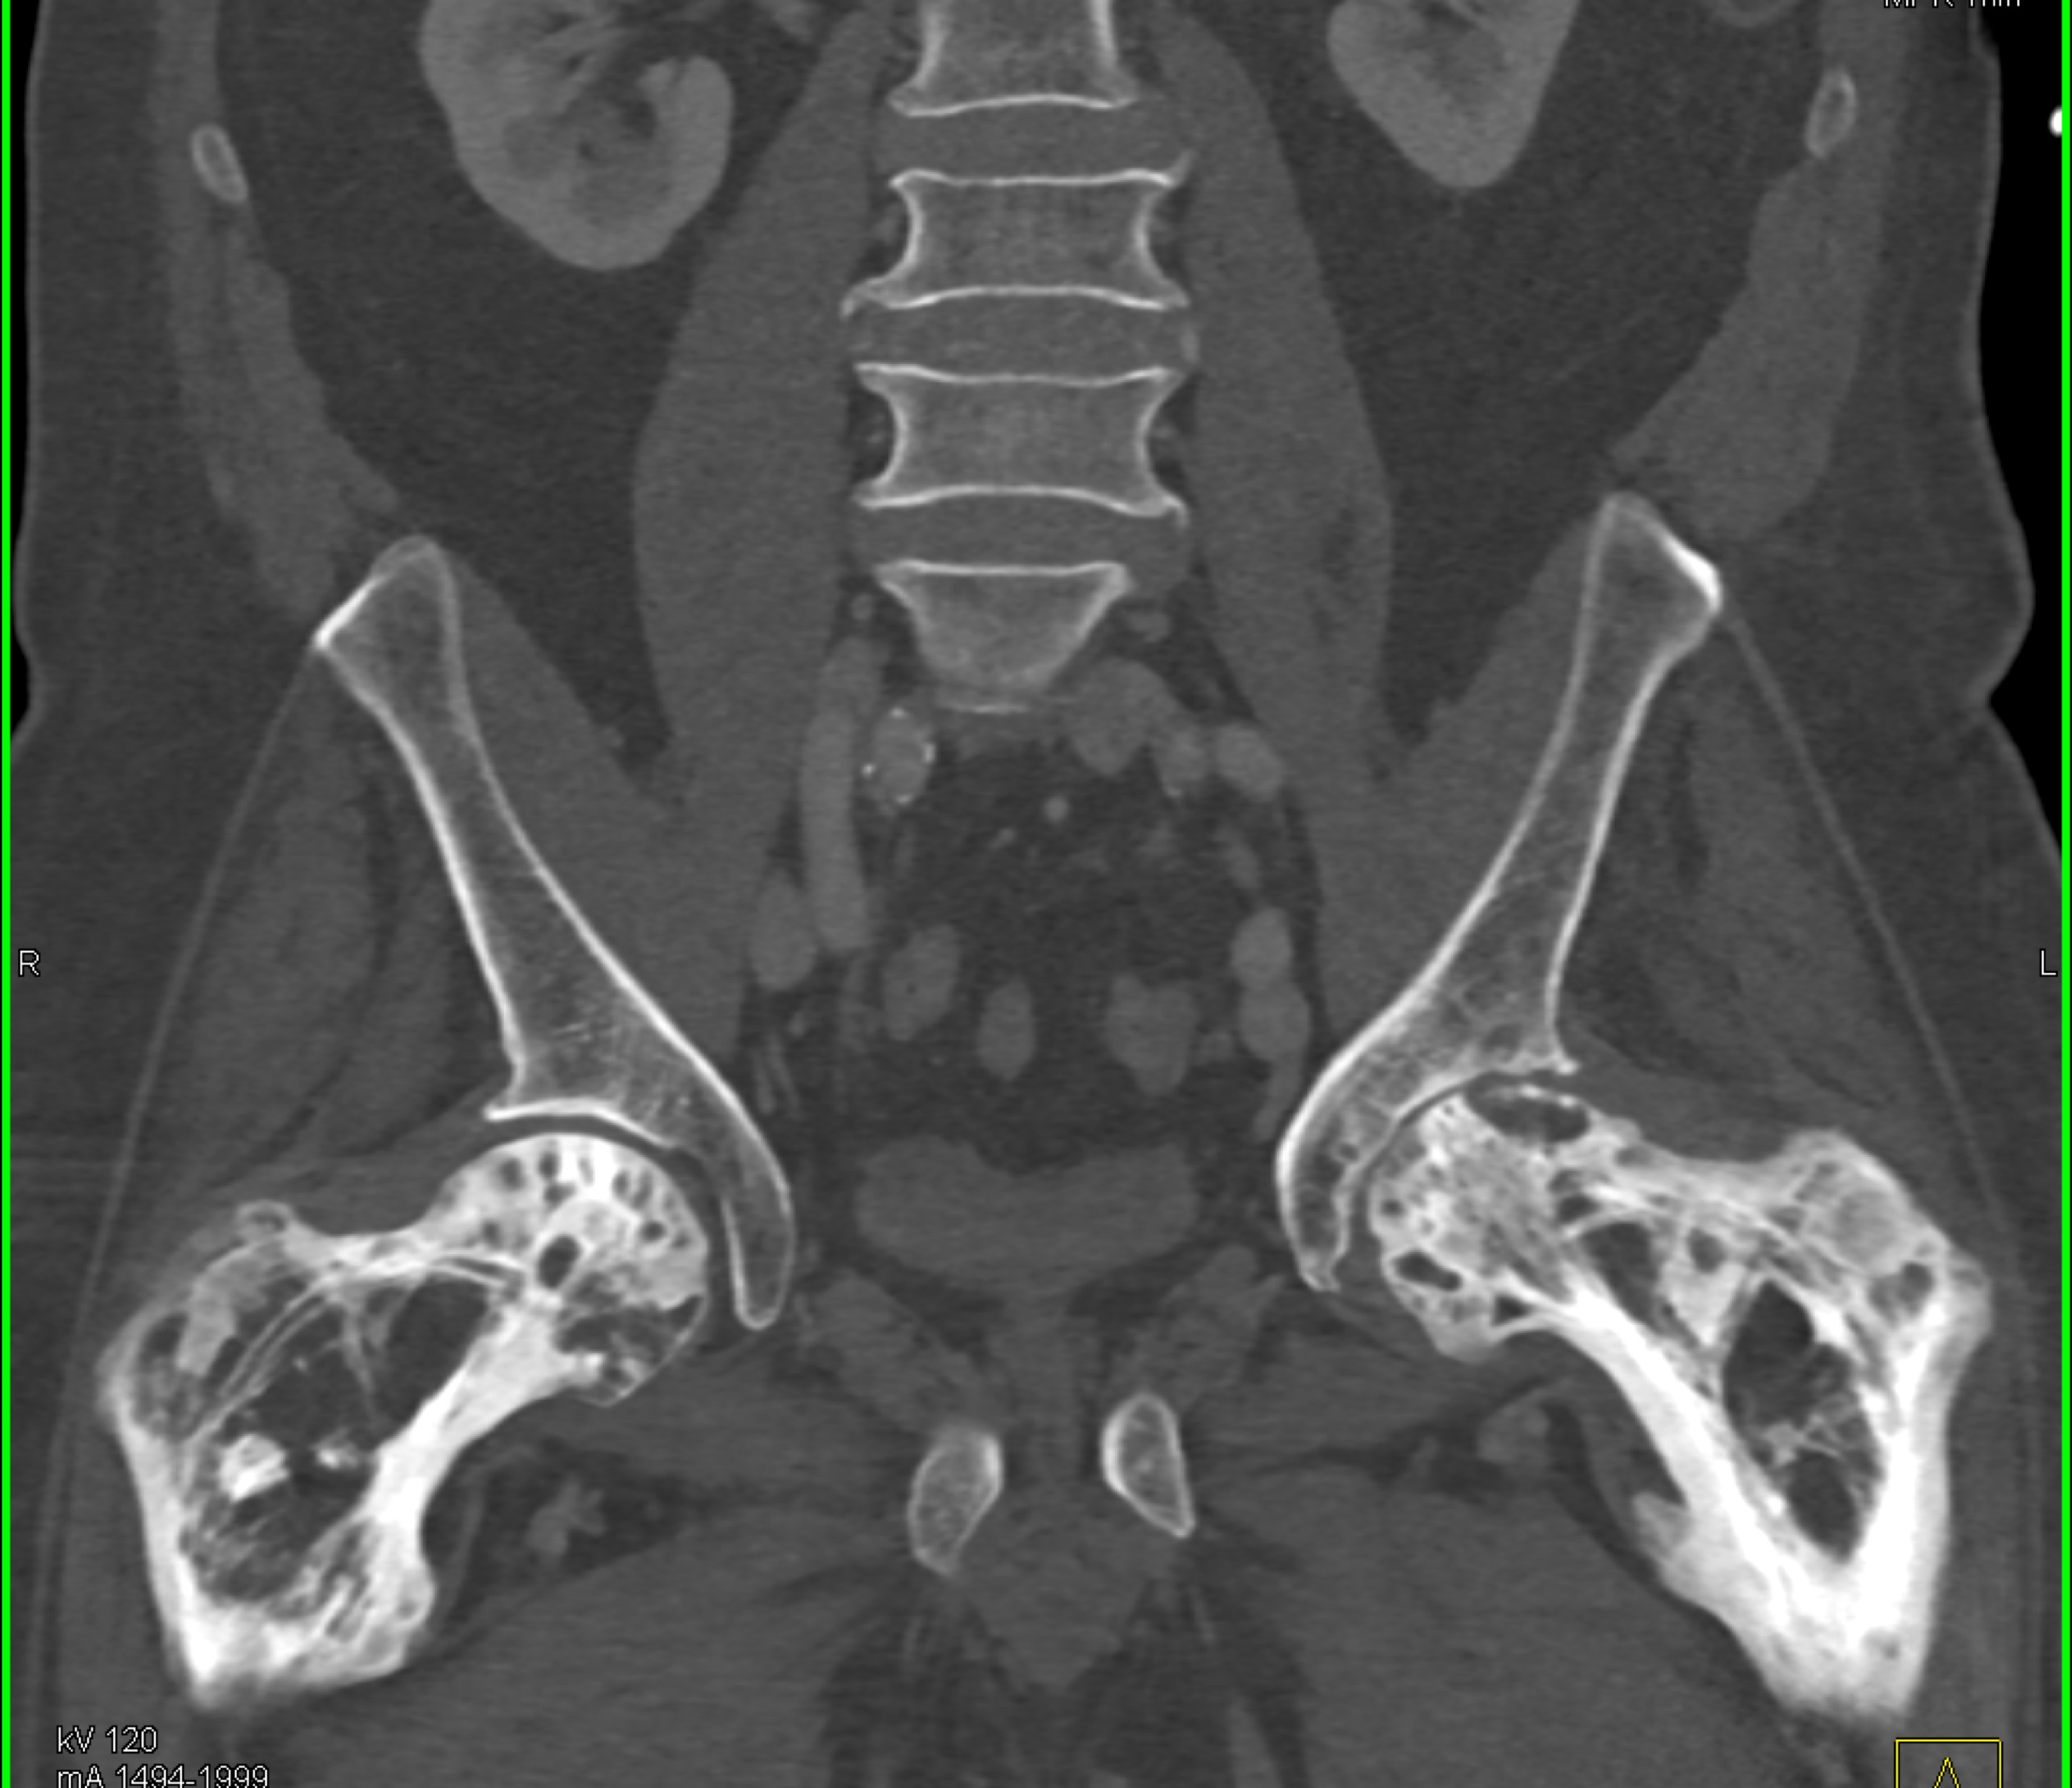

2) In this patient with a palpable right abdominal wall mass the best dx is?

rectus sheath hematoma

lymphoma

desmoid tumor

metastatic renal cell carcinoma